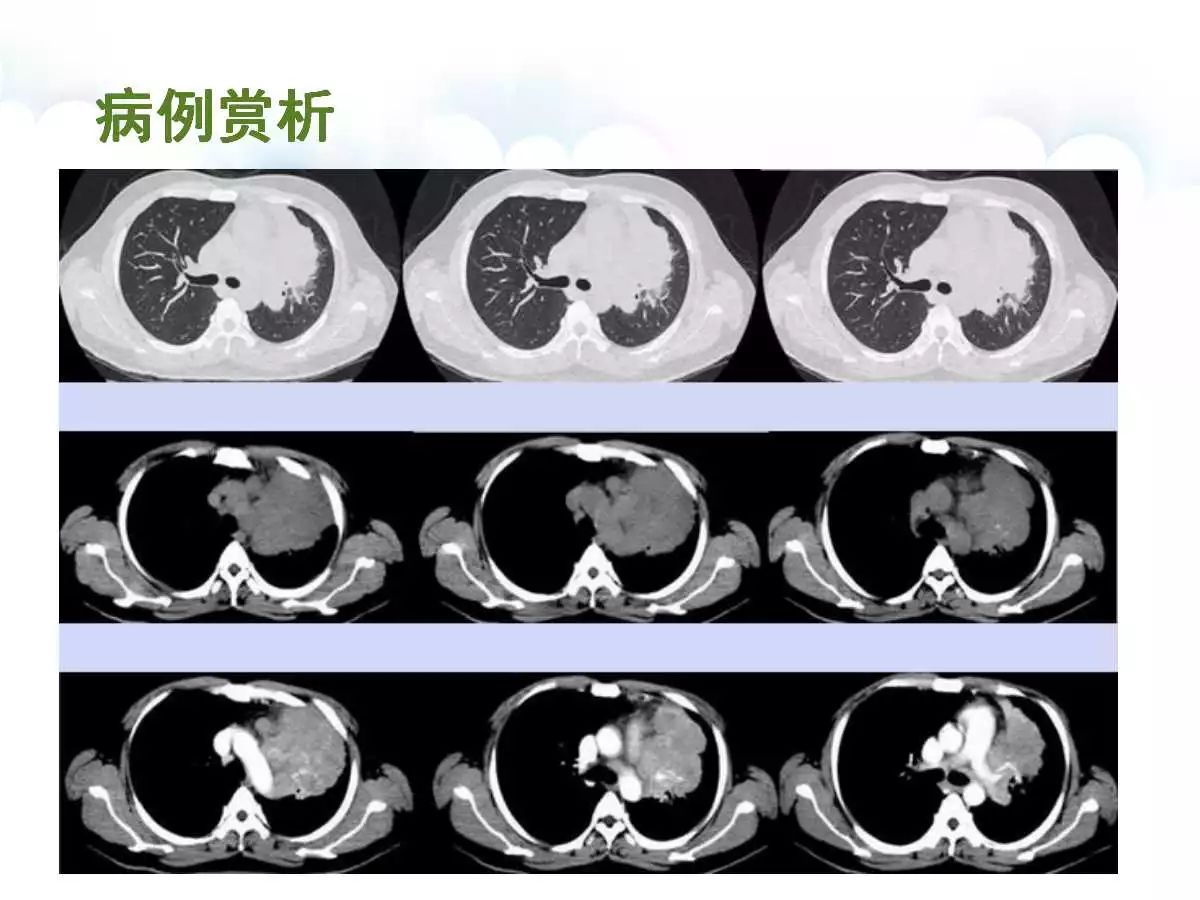

【病例】肺炎性肌纤维母细胞瘤1例CT影像表现